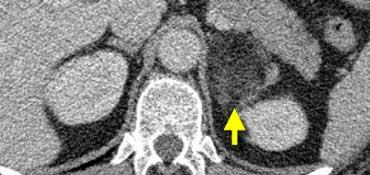

Trong 10% trường hợp, u tủy thượng thận có vôi hóa và thường có nhiều nang (mũi tên vàng).

Hình ảnh này cho thấy một trường hợp u tủy thượng thận khác với nhiều nang.